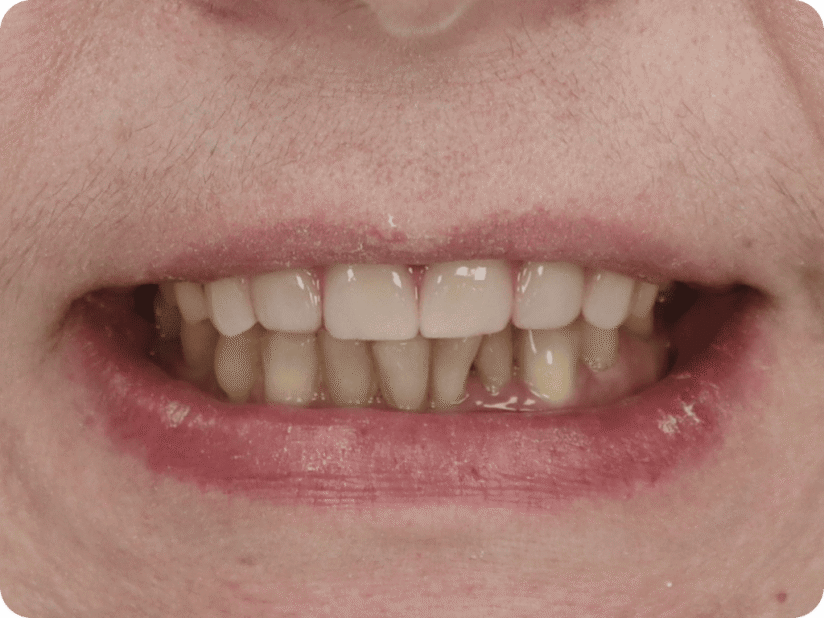

Установлен условно-съемый металлоакриловый протез на 12 зубов

Спустя 7 дней на верхней челюсти зафиксирован металлоакриловый протез из 12 зубов.